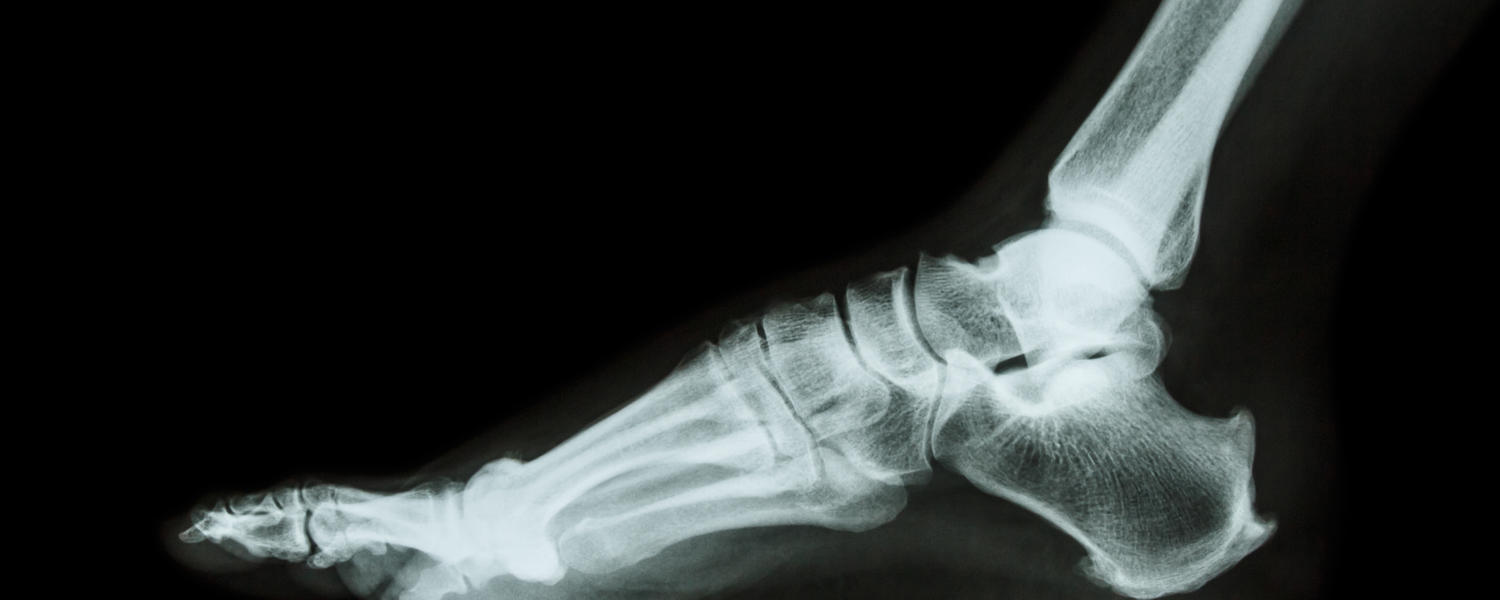

Our section has become a leading institution of the diabetic foot in Western Canada, with the Zivot Limb Preservation Clinic, located at the Peter Lougheed Centre, providing expert care for diabetic patients with foot ulcers and infection. The demand for high-risk diabetic foot care is growing as more attention is given to diabetic foot care and screening, and we are currently involved in two studies to help prevent diabetic foot ulcers and decrease their healing time.